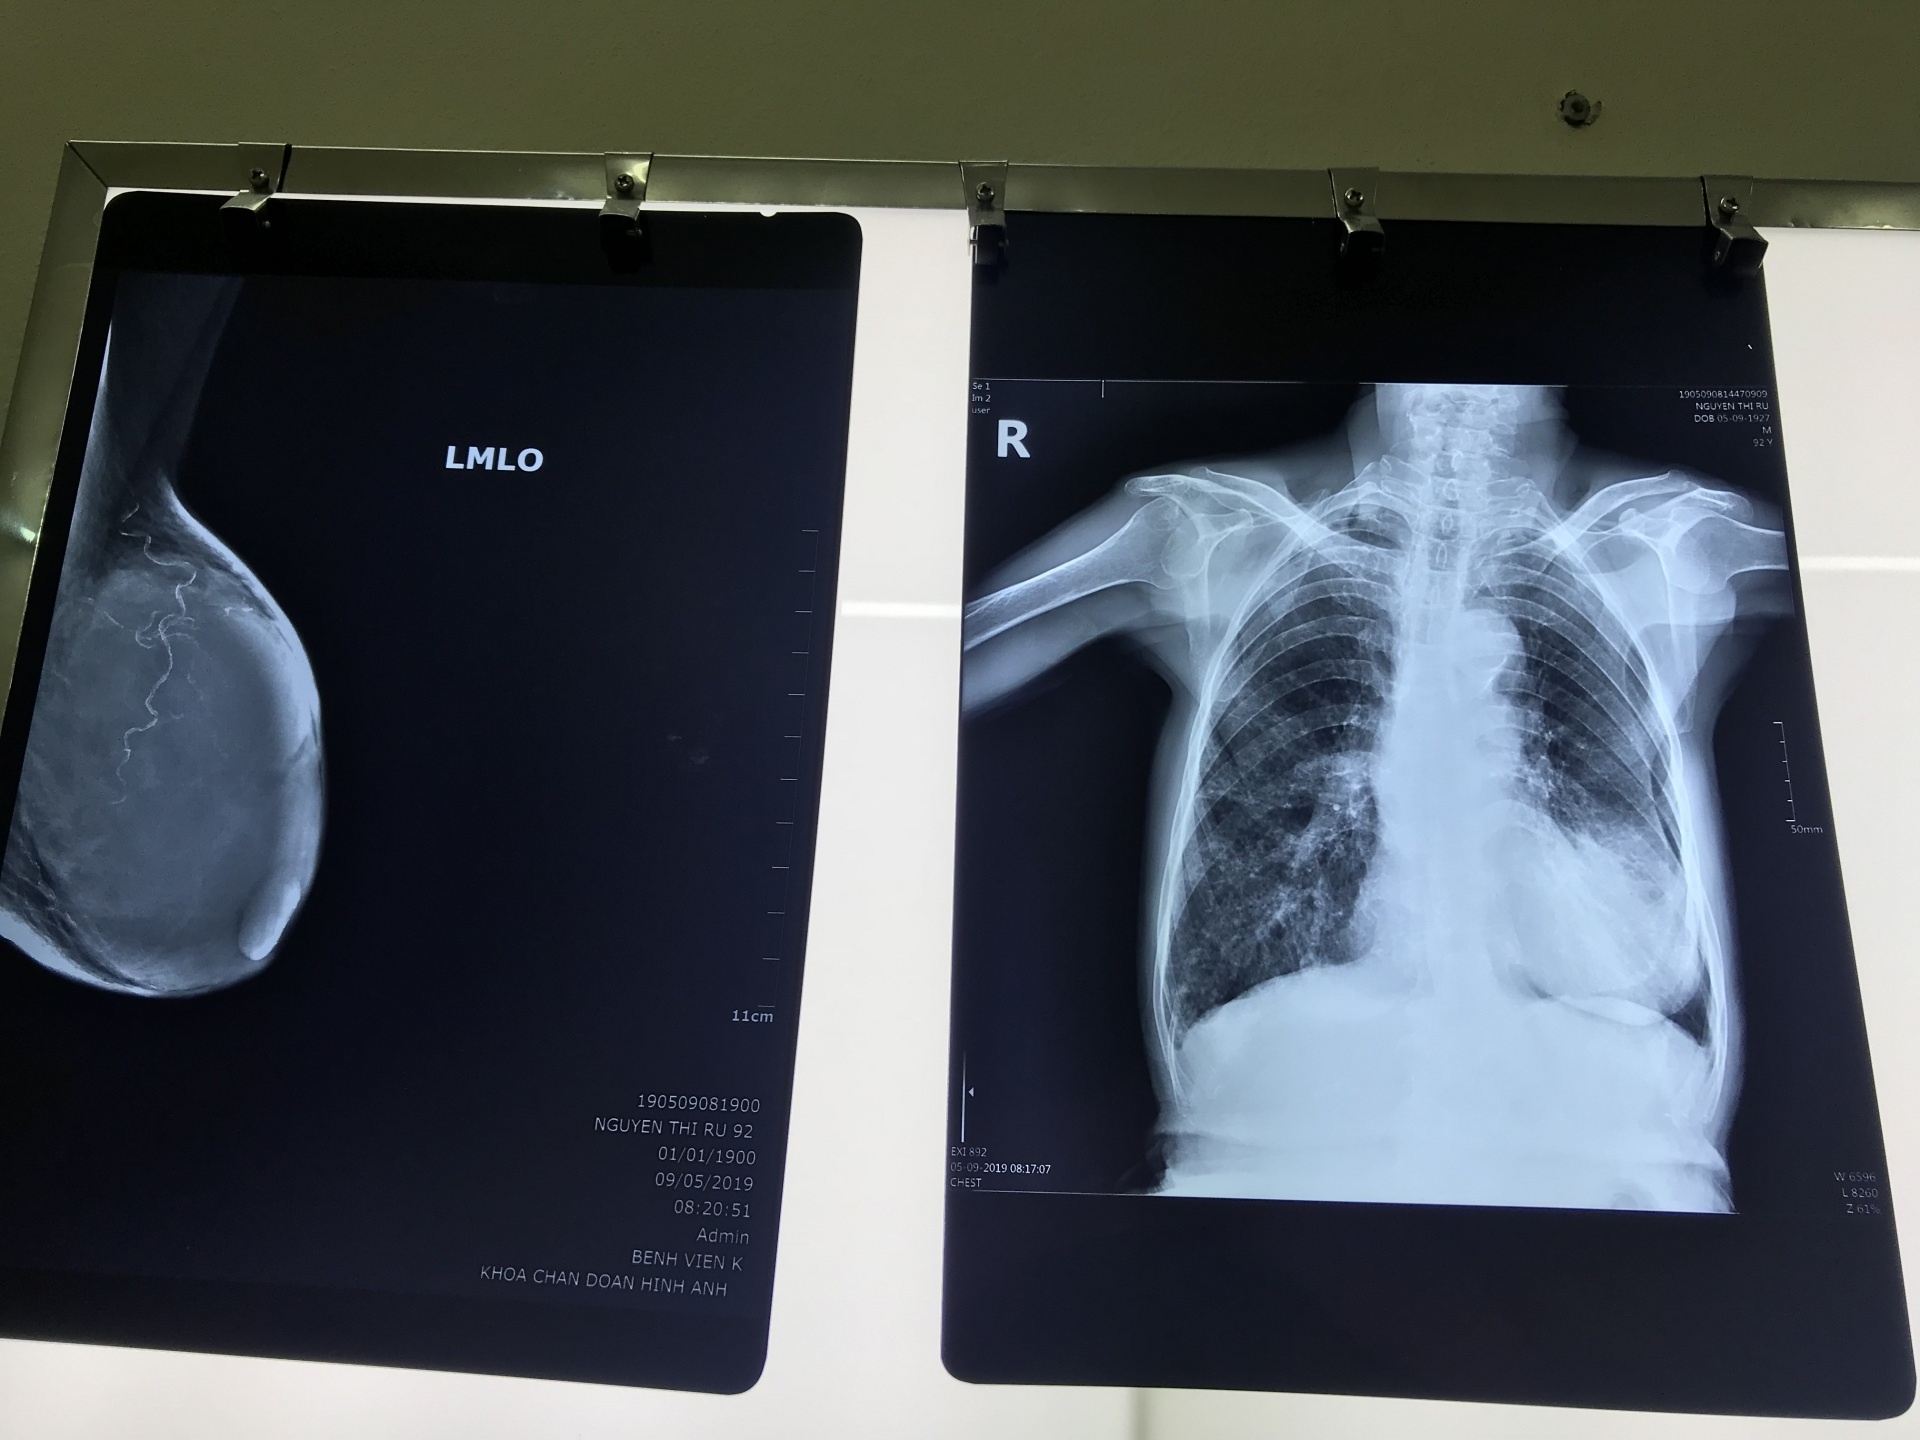

Đó là trường hợp của cụ bà Nguyễn Thị R. (92 tuổi) quê tại huyện Xuân Trường, Nam Định.

Theo người thân của bệnh nhân R. cho biết, đầu năm 2017, bà R. thấy đau tức vú nên gia đình đã đưa bà đi khám. Kết quả cho thấy có khối u 16x24mm tại vú trái, bác sĩ cũng tư vấn để gia đình điều trị cho cụ. Nhưng gia đìnhlo ngại bởi tuổi tác bà đã cao nên quyết định không phẫu thuật hay hóa xạ trị.

| Khối u chiếm toán bộ ngực trái bệnh nhân R. |

Chính vì tâm lý tuổi cao, không muốn con cháu lo lắng nên cụ R. gắng chịu những cơn đau suốt 2 năm. Đến năm 2019, khi không thể chịu đựng được do khối u ngày càng phát triển nhanh cụ mới đi khám lại.

Sau khi thăm khám, chụp chiếu, kết quả cho thấy khối u kích thước 10x6cm chiếm toàn bộ vú trái bệnh nhân R. Bệnh nhân được chẩn đoán ung thư vú giai đoạn tiến triển. Ngay lập tức các bác sĩ khoa Ngoại tổng hợp, Gây mê hồi sức cơ sở Tam Hiệp, Bệnh viện K đã tiến hành hội chẩn về trường hợp này.

Ca phẫu thuật cắt bỏ khối u của bệnh nhân R. diễn ra trong 2 tiếng đồng hồ. Các bác sĩ đã thực hiện cắt toàn bộ tuyến vú, loại bỏ tổn thương kích thước 10x6cm. Bệnh nhân hồi phục tốt, tiếp tục được theo dõi và điều trị.